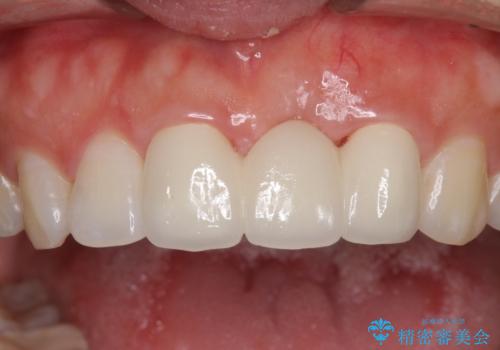

- 接着タイプの前歯のブリッジが不自然であるとのことで来院された患者様です。

欠損部の歯肉が窪んでいるため、歯肉移植により形態を改善し、オールセラミックブリッジにて補綴することとしました。

事前に装着されていた接着タイプのブリッジは、歯の切削量が少ない反面、接着界面から虫歯が進行しやすく、脱落リスクが高くなるというデメリットがあります。